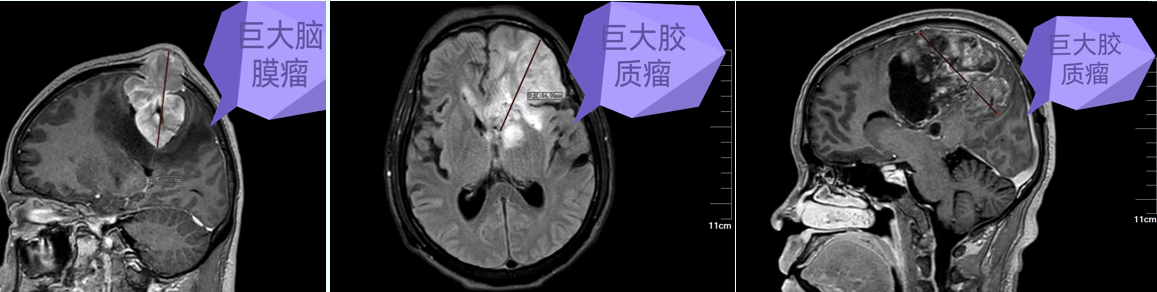

图片 5.png

神经导航引导下大脑半球巨大占位微创切除术

图片 6.png

神经导航引导下小脑半球巨大占位微创切除术

图片 7.png

挑战生命禁区,颅底、侧颅底占位微创切除术

从Ommaya囊侧脑室置入术到大脑半球、小脑半球占位切除术,从垂体瘤到颅底、侧颅底等复杂颅内占位切除术,凭借先进的微创技术与高精尖的设备,为众多患者解除了病痛,让患者重新找回了生活的精彩。

目前,肿瘤医院能熟练开展神经导航引导下、显微镜及神经内镜微创手术治疗各种神经肿瘤(脑膜瘤、胶质瘤、垂体瘤、听神经瘤、脑转移瘤、脑室系统肿瘤等);微型机器人引导下深部及重要功能区脑组织病变活检术;脑血管病(高血压脑出血、血管畸形、动脉瘤、烟雾病)及颅脑损伤手术;各种类型脑积水的分流手术;面肌痉挛、三叉神经痛、痉挛型脑瘫、帕金森、脑梗死的诊治;脑脓肿、椎管内感染等各种复杂的颅内感染性疾病的综合治疗;去骨瓣减压术后钛网或PEEK材料颅骨修补术;频发型癫痫的迷走神经刺激术(VNS);癌痛、昏迷促醒治疗等。